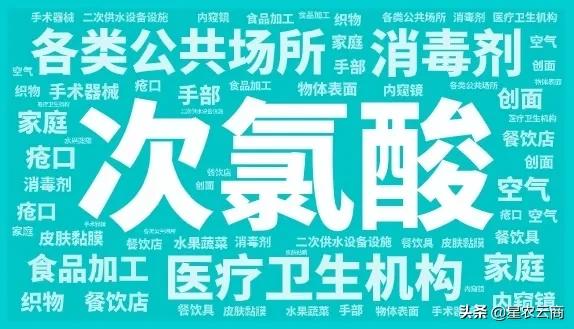

次氯酸消毒剂适用于医疗卫生机构、公共卫生场所、和家庭的一般物体表面、医疗器械、医疗废物、食饮具、织物、果蔬和水等的消毒,还可用于空气、二次供水设备设施表面、手、皮肤和黏膜的消毒。